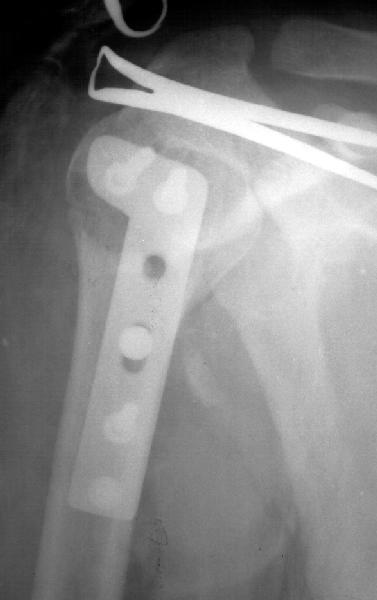

A male 25 y.o. after a car accident Aug 16, 2002 sustained a fracture of the proximal humerus (image 1), Sep 5 ORIF performed elsewhere.

Image 2